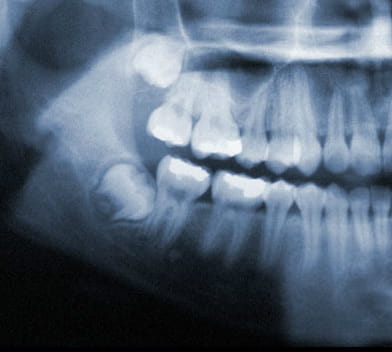

X-Ray of wisdom teeth

Wisdom teeth generally begin to form in your pre-teen years. By late teen years, the crown of the wisdom teeth will begin to erupt through the gums if there is adequate room. By mid twenties, your wisdom teeth will either be able to fully erupt or will have become impacted. Early removal of wisdom teeth makes the procedure easier for the patient to tolerate and promotes faster healing after wards. By your early forties, the wisdom teeth roots have become fully anchored to the jawbone and if required to be extracted, will be much harder and will need more time to heal.

Wisdom teeth under ideal circumstances should grow in straight like any other tooth. However, it is common for wisdom teeth to become impacted inside the jaw or just under the gums. If this occurs, your wisdom teeth should be removed.